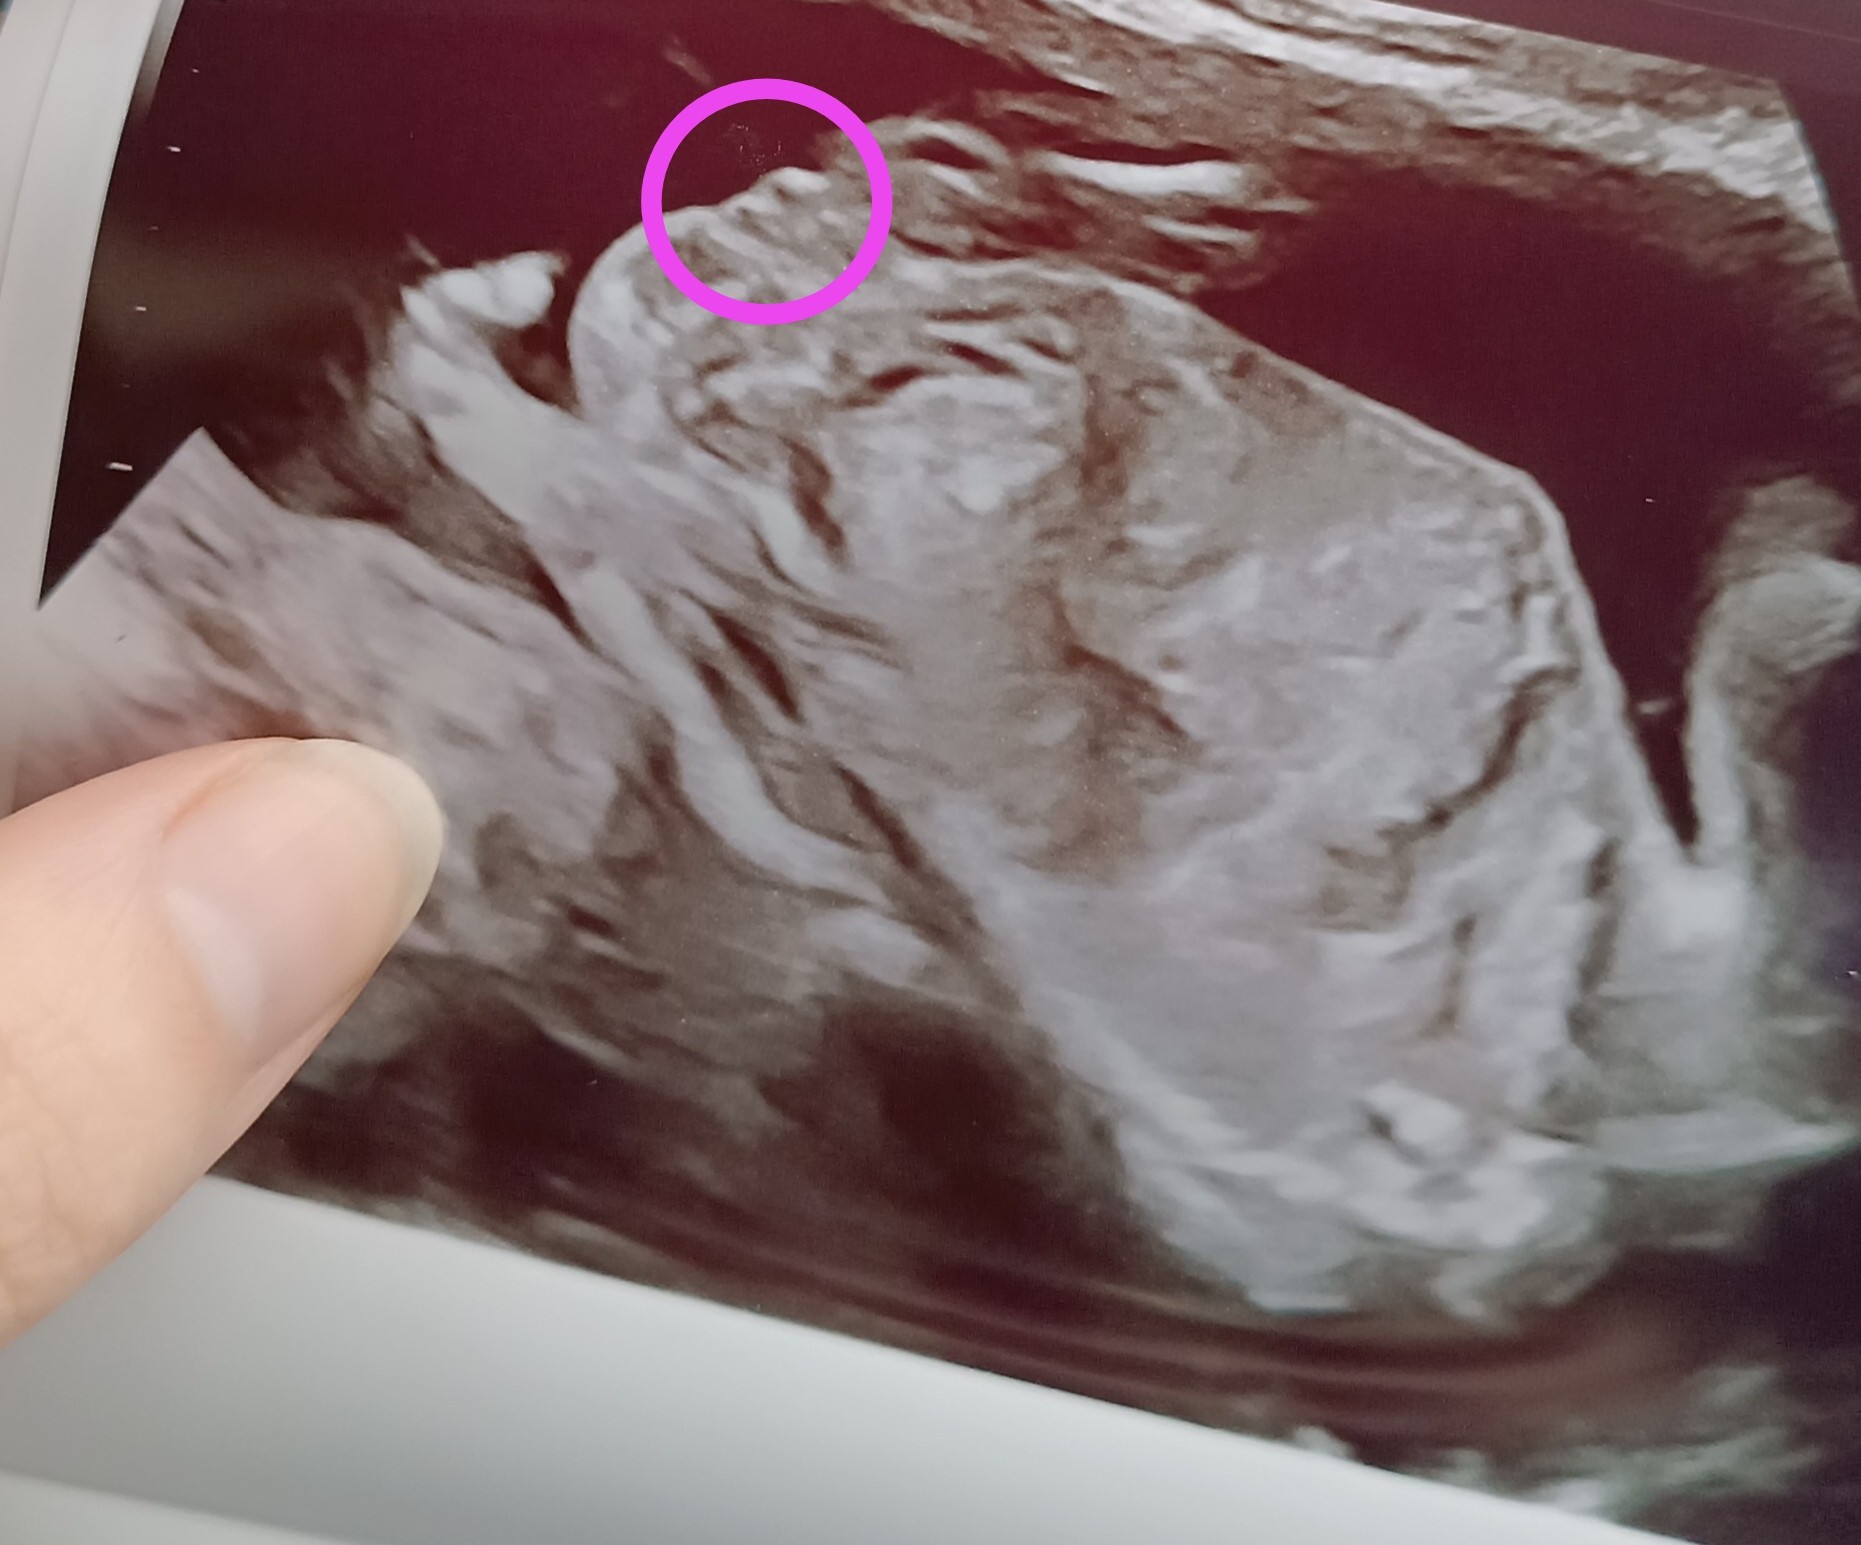

Hej , byłam dziś na badaniu połówkowym, badanie masakra nic się nie dowiedziałam tylko to ile waży maleństwo i to że to chłopiec ?!

Posiadam również dwa zdjęcia USG ... Cały dzień dziś mam mętlik w głowie i nie wiem co myśleć ...

Wrzucam zdjęcia z poprzednich USG